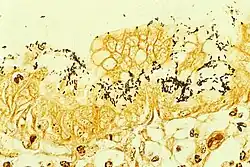

Der direkte Nachweis des H. pylori geschieht durch Probeentnahmen (Biopsien) aus dem unteren Magendrittel und Mikroskopie. Auch kann aus den Proben mittels des Helicobacter-Urease-Test auf das Vorhandensein der Urease geschlossen werden und damit indirekt auf das Vorhandensein des Bakteriums.